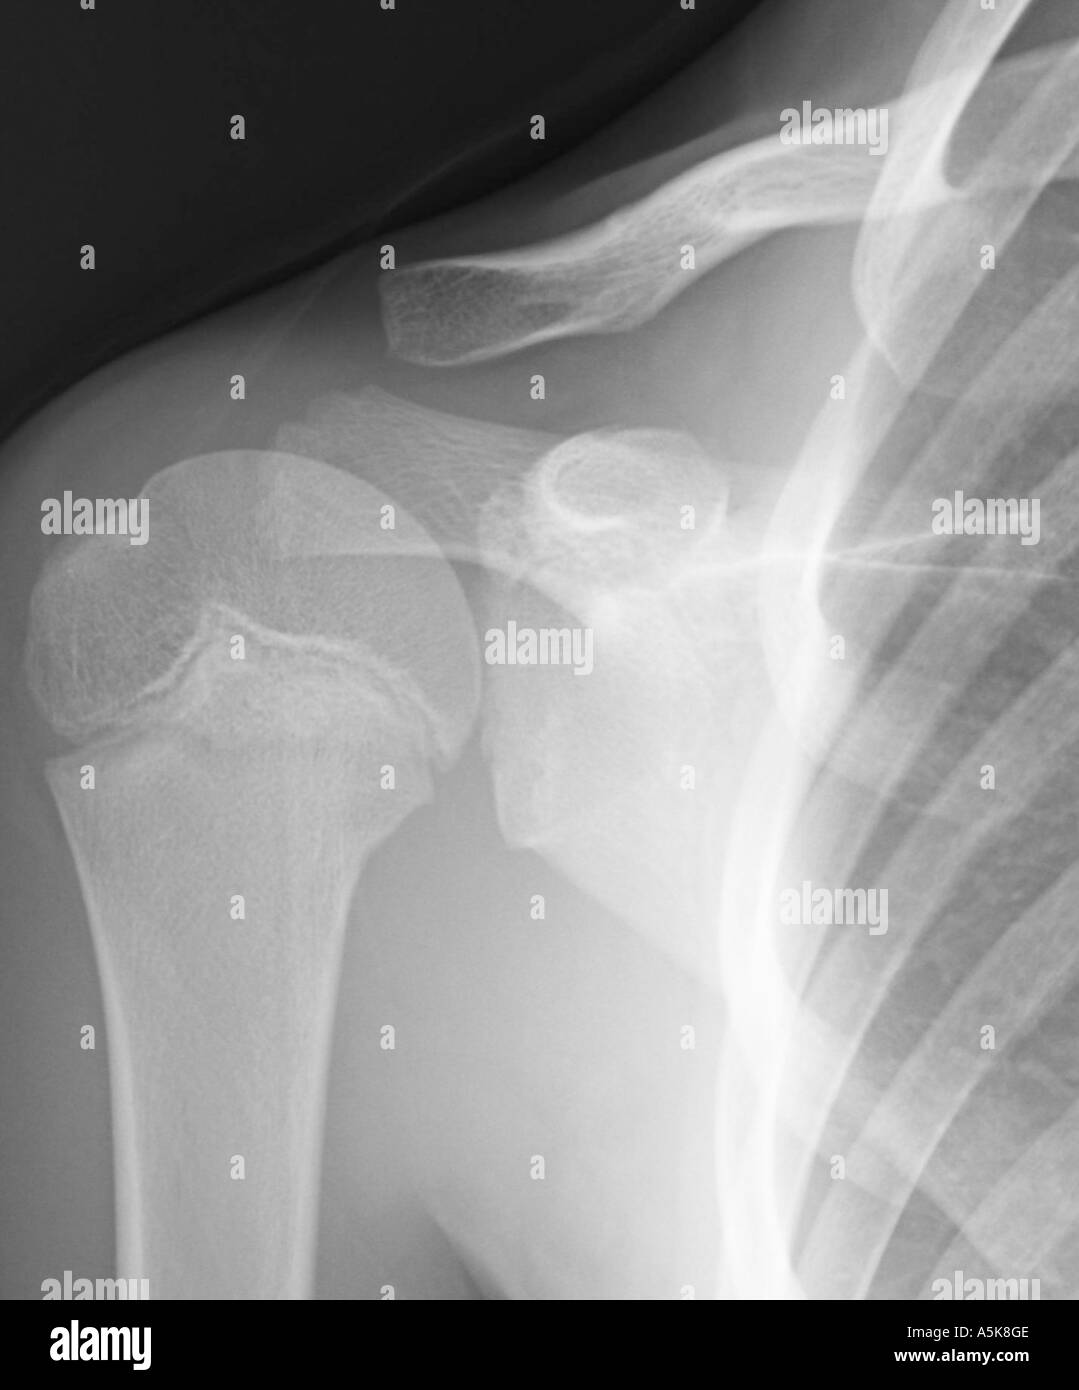

X Ray of young boys right shoulder Stock Photo Alamy Shoulder X Ray In Child little league shoulder affects the physis of the proximal humerus. Our comprehensive guide will teach you the. this is a repository of normal pediatric bone xrays and their examples for a quick reference look. This is most commonly seen in skeletally immature. One is able to visualize 90% of posterolateral humeral. shoulder x ray paediatric the anteroposterior. Shoulder X Ray In Child.

Shoulder xray shows an arm fracture (numeral neck) in a child who Shoulder X Ray In Child the evaluation of traumatic shoulder injury in children and adolescents will be discussed here. shoulder x ray paediatric the anteroposterior shoulder view in pediatrics is part of a two view series examining the shoulder joint,. Our comprehensive guide will teach you the. One is able to visualize 90% of posterolateral humeral. This is most commonly seen in skeletally. Shoulder X Ray In Child.